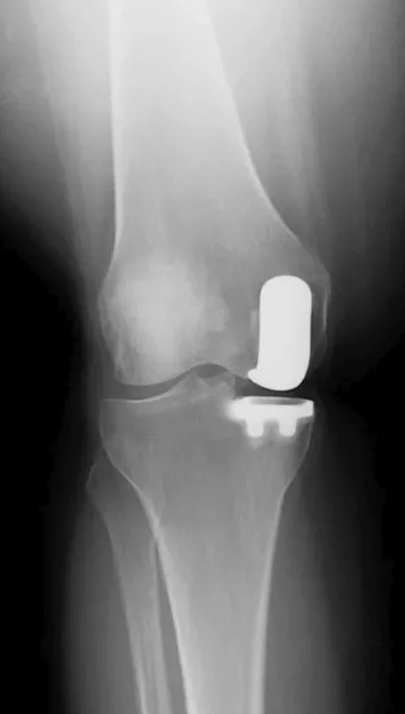

Почему мы выбираем эндопротез Матис (Мathys)?

— Эндопротез Матис обеспечивает анатомически правильное положение и учитывает кинематику сустава. Это позволяет восстановить естественную ориентацию суставной щели и достичь физиологической стабильности коленного сустава без мобилизации мягких тканей.

BalanSys UNI — это модульная система для цементного одномыщелкового эндопротезирования коленного сустава. Минимально инвазивный частичный эндопротез сустава позволяет сохранить крестообразные связки, обеспечивая естественную проприоцепцию. Конструкция бедренного компонента balanSys UNI имеет два радиуса в сагиттальной плоскости для анатомической реконструкции как дистального, так и заднего мыщелков бедренной кости и поддержания глубокого сгибания колена